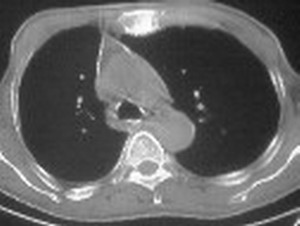

右肺下叶支气管阻塞,右下叶不张,考虑中心型肺癌伴下叶不张

先考虑:右下肺中心型肺癌伴下叶肺不张、胸腔积液

右肺下叶支气管闭塞,中间段支气管狭窄,下叶不张,胸腔及叶间积液.中心型肺癌伴下叶肺不张.胸腔和叶间积液.

考虑中心型肺癌伴下叶不张

考虑:右下肺中心型肺癌伴下叶肺不张、胸腔积液

考虑中心型肺癌伴下叶不张,肺底积液吧。

考虑右下肺中心型肺癌伴下叶肺不张、胸腔积液。